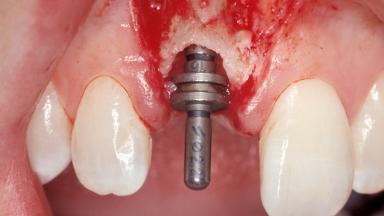

Immediate Placement of an Implant in a Maxillary Right Central Incisor Site

A 30-year-old female patient was referred to the office for the treatment of tooth 11. Her chief concern at the initial visit was to inquire, “Why is my tooth pink?” Upon clinical examination, it was determined that tooth 11 had a previous history of trauma and that the clinical crown had become noticeably pink in color as a result of internal resorption. This diagnosis was confirmed radiographically, indicating a large radiolucency involving the central and distal portions of the clinical crown. It was determined that restoration of this tooth was not possible, and that extraction was indicated. The presence of a mid-line diastema, which the patient wanted to reproduce, directed the treatment plan for tooth replacement utilizing a dental implant.

Type of Implants One-Piece|Reduced-Diameter

Attachment One-Piece|Reduced-Diameter

Abutment Type Standard

Placement Protocol Immediate implant placement

Retention Screw-retained Screw-retained